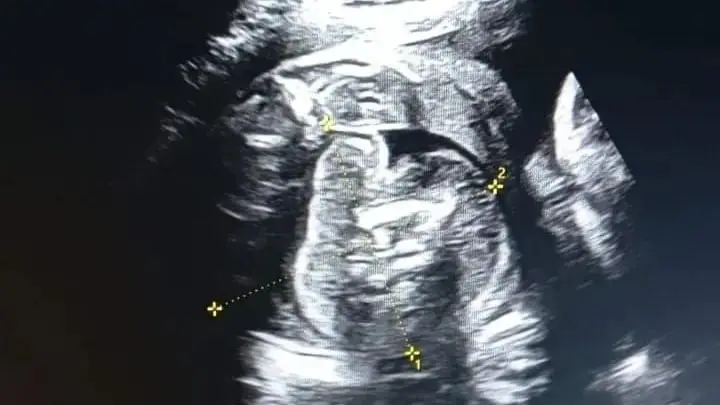

ভারতের মহারাষ্ট্রে এক নারীর গর্ভে থাকা শিশুর শরীরে আরও একটি ভ্রূণের সন্ধান পাওয়া গেছে। সম্প্রতি ওই নারী সোনোগ্রাফি করানোর জন্য হাসপাতালে যান। তখন চিকিৎসকরা এ বিষয়টি লক্ষ্য করেন।

জানা যায়, ৩২ বছরের ওই নারী তার গর্ভাবস্থার অষ্টম মাসে সোনোগ্রাফি করাতে গত বুধবার হাসপাতালে যান। তখন পরীক্ষা করে জানা যায়, ওই নারীর গর্ভে যেমন একটি শিশু রয়েছে, তেমনই ওই শিশুর গর্ভেও একটি ভ্রূণ রয়েছে। বিষয়টি সম্পর্কে নিশ্চিত হতে চিকিৎসক এবং বিশেষজ্ঞদের একটি টিম আরও একবার সোনোগ্রাফি করেন। তখনও গর্ভে থাকা শিশুটির গর্ভে একটি ভ্রূণ স্পষ্টভাবে দেখা যাচ্ছিল।

হাসপাতালের এক শল্যচিকিৎসক (সিভিল সার্জন) বলেছেন, সোনোগ্রাফি পরীক্ষার পর দেখা যায়, ওই নারীর গর্ভে একটি শিশু রয়েছে এবং শিশুটির গর্ভে আরও এক শিশু রয়েছে। তবে একে ঠিক শিশু বলা যাবে না, কারণ এটি ফিটাল মাস। এক অর্থে বলতে গেলে, এটি একটি মাংসের পিণ্ড।

‘এটি জীবিত শিশু নয়, কারণ তার হৃদস্পন্দন নেই। দেখতে শিশুর মতো মনে হয় বলেই একে বেবি বলা হয়।

বিষয়টিকে আরও বিশদে ব্যাখ্যা করে তিনি বলেন, ওই মাংসপিণ্ড আকারে বৃদ্ধি পাচ্ছে, কারণ সেখানে রক্ত সরবরাহ অব্যাহত রয়েছে। ডাক্তারি ভাষায় একে ফিটাস ইন ফেটু (ভ্রূণের অভ্যন্তরে ভ্রূণ) বলা হয়।